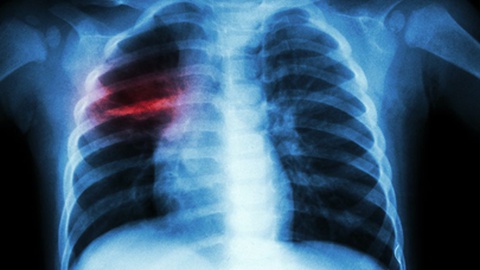

Tuberculose mata 1,2 milhões de pessoas em 2023 e ultrapassa a covid-19

Cerca 1,2 milhões de pessoas morreram e quase 11 milhões adoeceram com tuberculose em 2023, ano em que a doença destronou a covid-19 como a principal causa de morte devido a um único agente infeccioso.

A tuberculose é uma doença infecciosa que se transmite maioritariamente por via inalatória, ou seja, pela inalação de gotículas expelidas pela pessoa doente quando tosse, fala ou espirra.